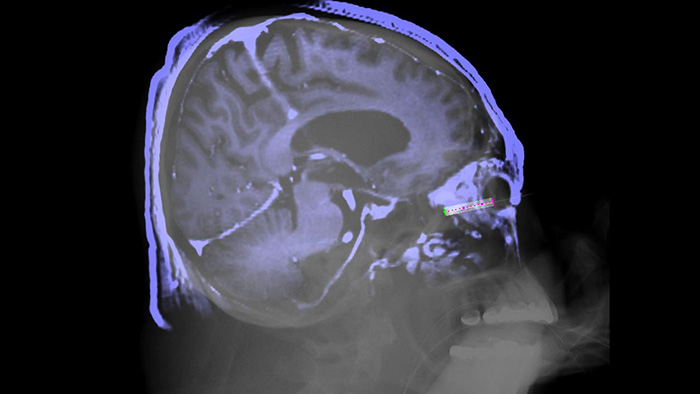

XperGuide

XperGuide offers live 3D image needle guidance, letting you bring percutaneous needle procedures into the Hybrid OR. It overlays live fluoroscopy and 3D soft tissue imaging data from previously acquired CT or MR scans or Philips XperCT, providing information on the needle path and target.